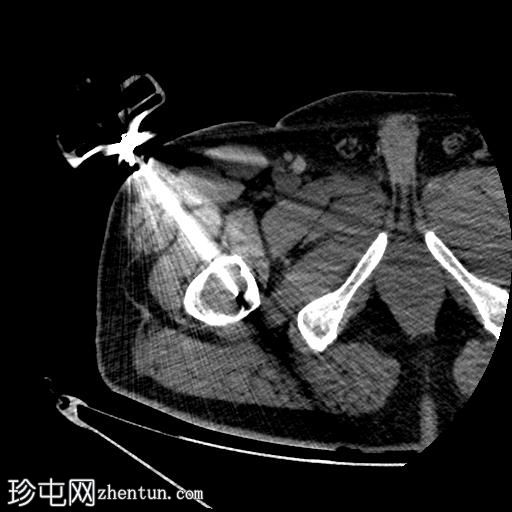

轴位

平扫

行CT引导下病变穿刺活检,术中及术后均未见并发症。

将活检针置于右股骨近端干骺端溶骨性透亮肿块中心后,从囊性病变中抽取血液。穿刺活检结果为阴性,未见骨髓浸润。因此,囊性病变的血液样本被送检进行组织病理学检查,结果显示无恶性肿瘤

根据CT影像学表现和组织病理学结果,应考虑右股骨干近端良性囊性骨病变。